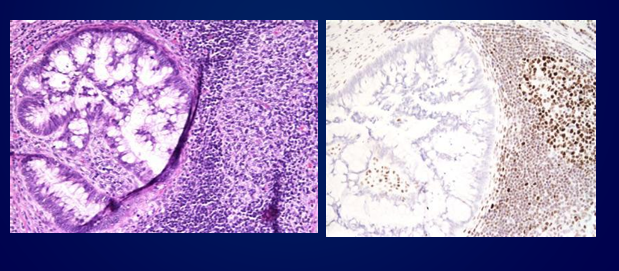

pathology features of lynch-related CRC

“screening for lynch syndrome” with molecular tumor testing

-CRC with loss of MSH2 protein expression